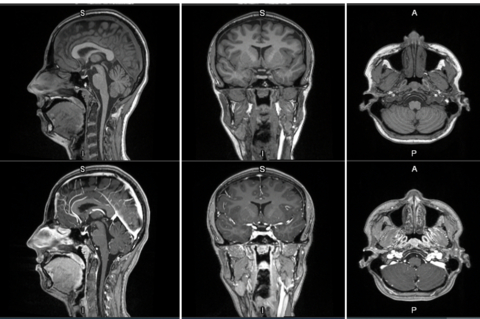

CHICAGO, IL, August 04, 2025 /24-7PressRelease/ — Cluster Headaches and Migraines are just 2 of the severe headaches secondary to the Trigeminal Nervous System Dysfunction and/or Nociception. The Trigeminal Nerve, also known as the “Dentist’s Nerve” is responsible for almost 100% of severe headaches and facial pain directly.

The Trigeminal Nerves are also a major center for proprioception of the head and upper cervical regions.

Headaches accompanied by dizziness or vertigo can be a sign of vestibular migraine, a trigeminal/ autonomic neurological condition causing dizziness and balance issues. These symptoms can also be associated with other conditions like Meniere’s disease, BPPV, or even anxiety.

Sphenopalatine Ganglion Blocks have over 100 years safety record in treating these disorders and work especially well in conjunction with Neuromuscular Dentistry approach to correcting underlying causes including nociceptive (pain) input into the brain.

The Sphenopalatine Ganglion or SPG can be accessed through the nose with Cotton-Tipped Catheters to control the Autonomic aspects of these disorders. While the SPG is the largest Parasympathetic Ganglion of the head it also has Sympathetic Nerves coming from the Stellate Ganglion and Cervical Sympathetic Chain via the Superior Sympathetic Ganglion. The SPG also containes Somatic Fibers from the Maxillary Division of the Trigeminal Nerve.